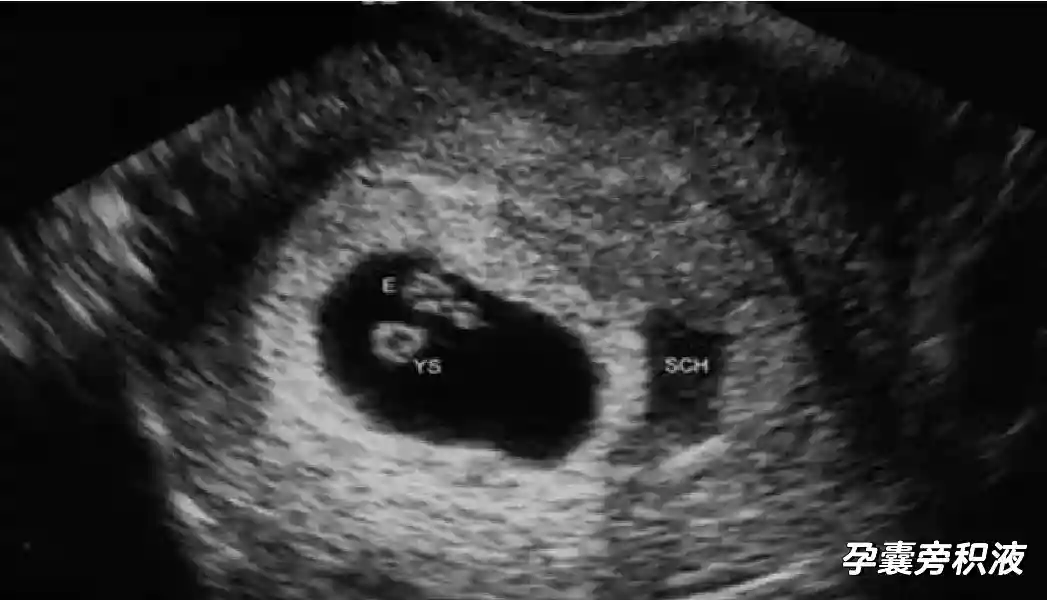

2??卵黄囊:是妊娠囊内第一个解剖结构,直径<7mm。表现为小环状,中央为无回声,囊壁薄,内透声好。卵黄囊位于胚胎旁胚外体腔内。卵黄囊通常在孕5-6周时出现,5-10周稳步增长,一般不超过7mm,至12周消失。妊娠囊的大小与卵黄囊之间有一定关系,妊娠囊平均直径> 8 mm 时,经阴道超声均应显示卵黄囊,妊娠囊平均直径> 18 mm 时,经腹超声均应显示卵黄囊。

3??胚胎:胚胎通常在6-7周时可以为超声显示,起初为胎芽,表现为卵黄囊一侧局部组织增厚,达到1 -2 mm 时才有可能为超声测量出来。达4-5mm时可见胎心搏动,相应孕周为6-6.5周,妊娠囊大小为13-18mm。胚芽长度≥7㎜时仍未见心管搏动,提示胚胎停止发育。胚胎的出现和妊娠囊直径的关系:妊娠囊直径> 16 mm 时,经阴道超声应显示胚胎。妊娠囊直径> 25 mm 时,经腹超声均应显示胚胎。